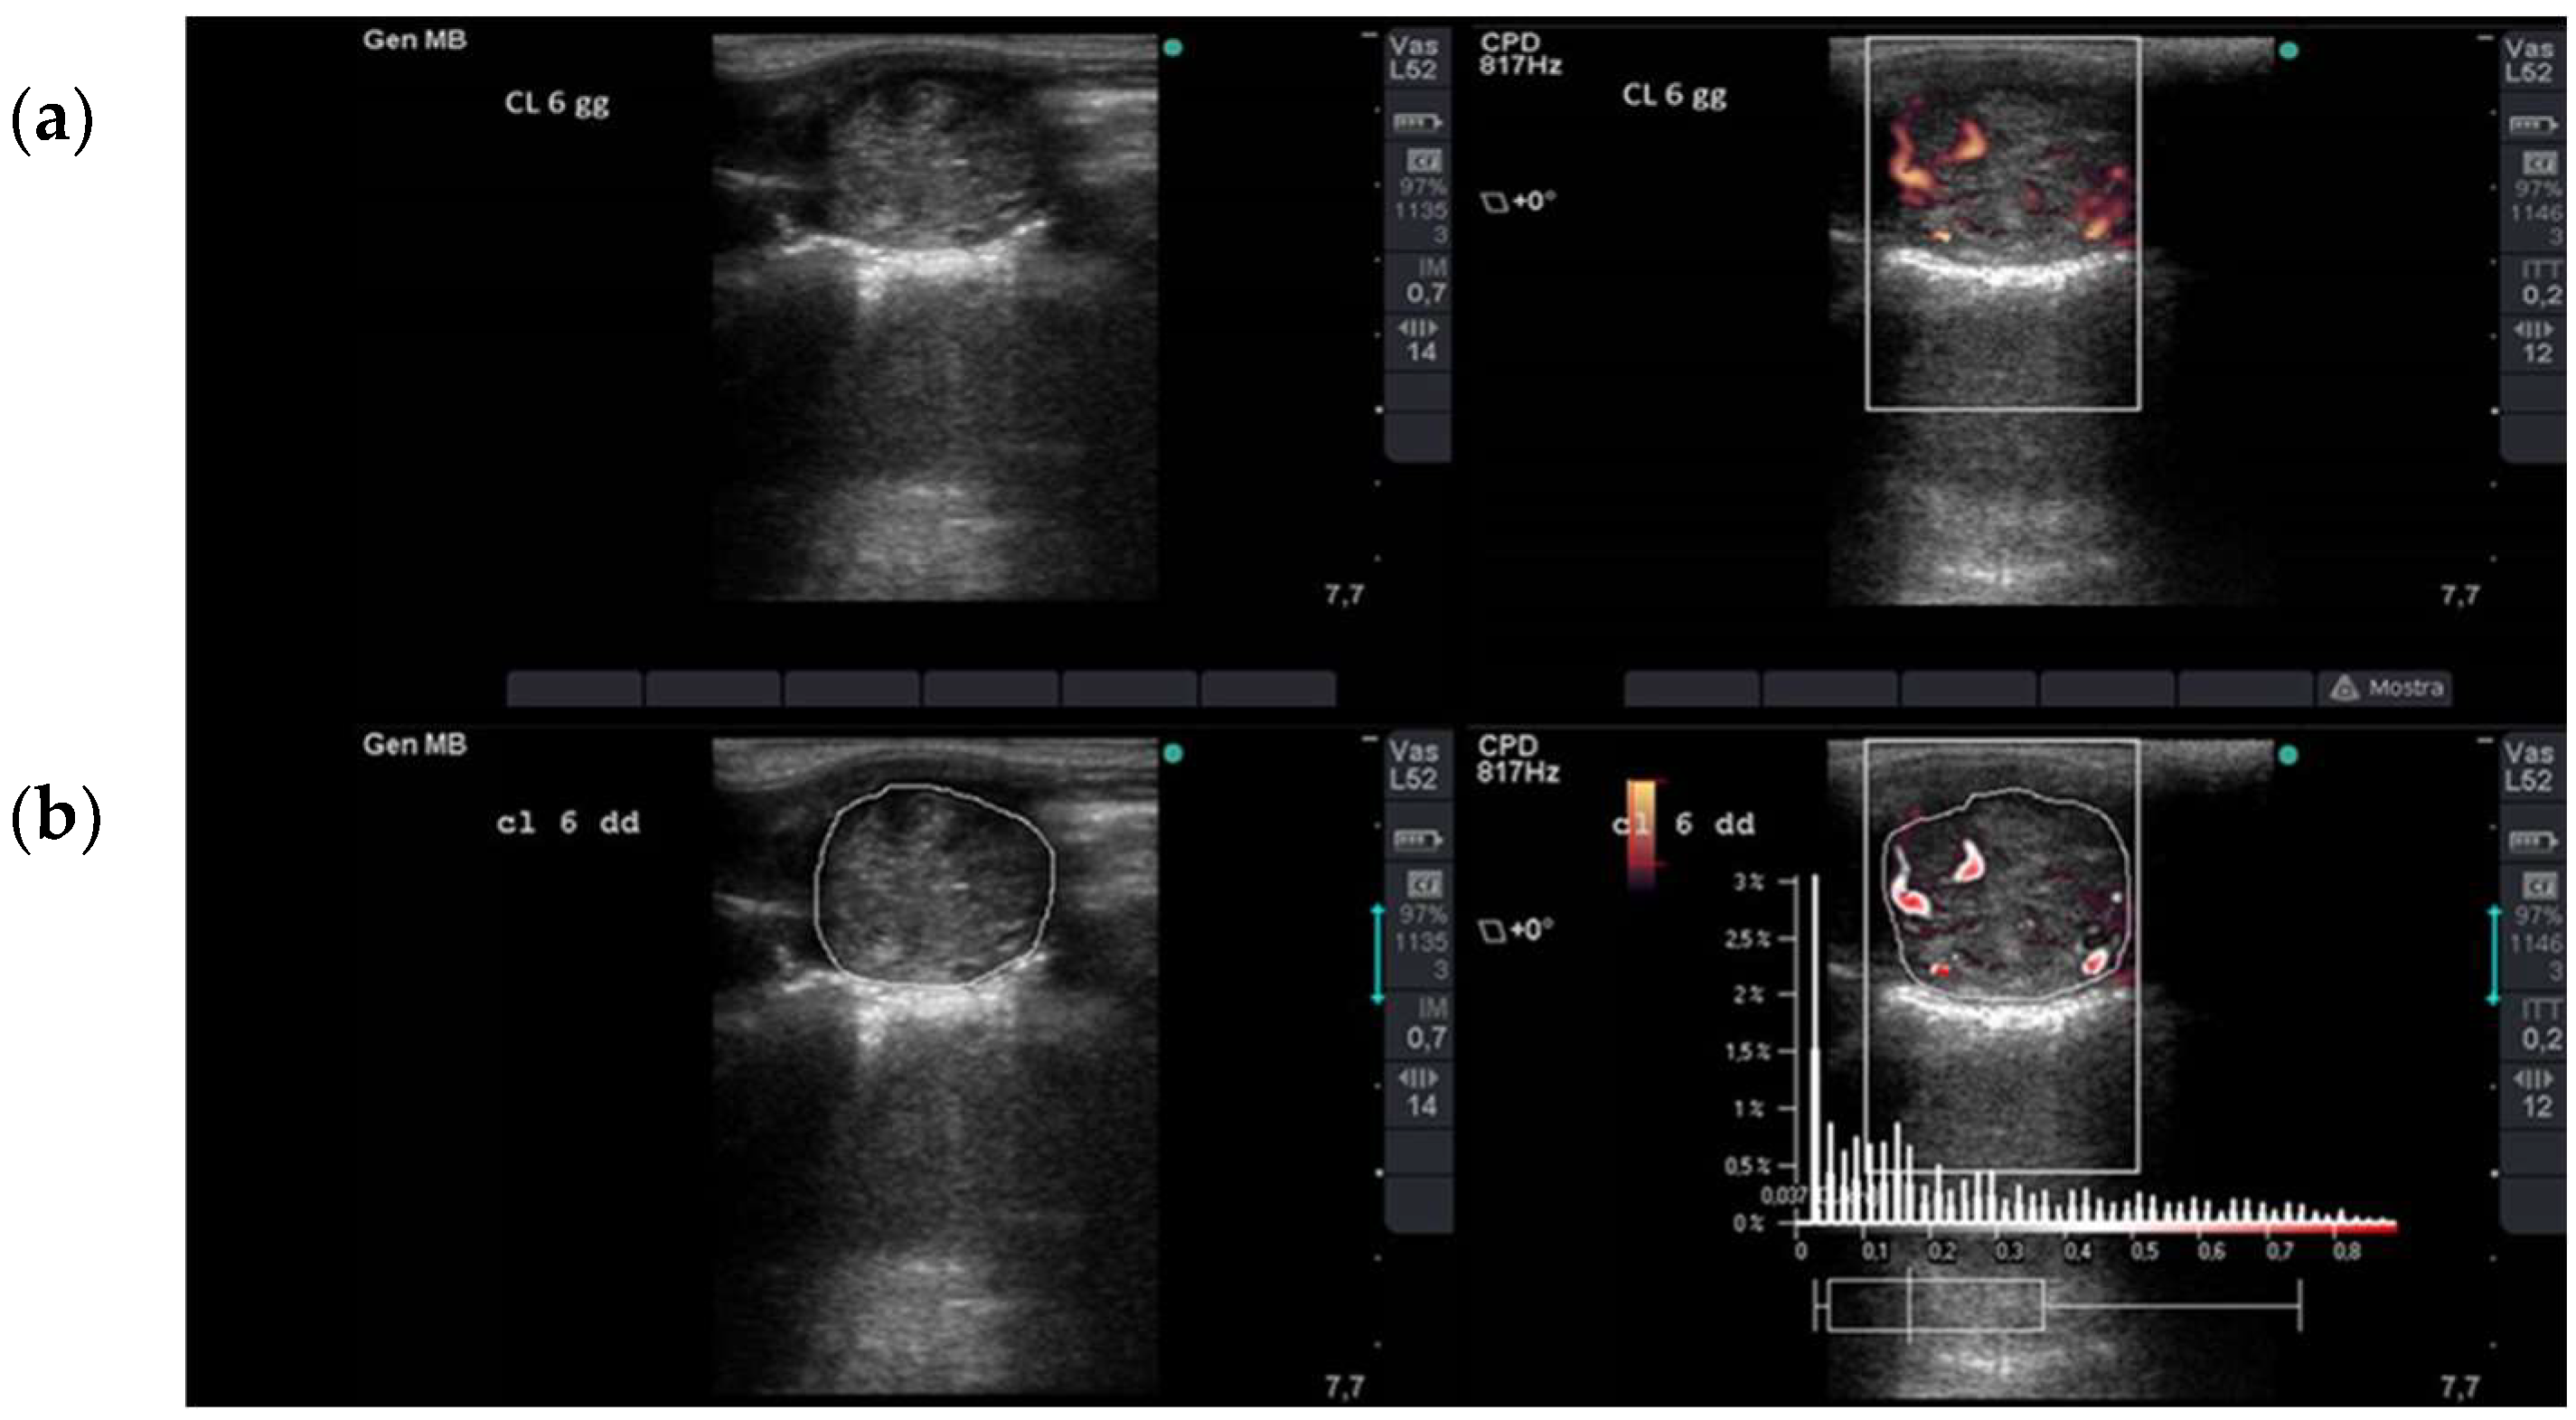

2.2. Ultrasonographic Assessment of Luteal Blood Flow